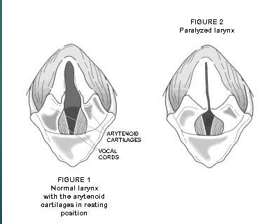

Laryngeal paralysis

Loss of motor function of the larynx

Causes a narrowing of the larynx so is harder for their air to move through

Most commonly seen in large breed dogs

Laryngeal paralysis can be caused by ..

Polyneuropathy

Trauma

Iatrogenic - neck surgery

Hypothyroidism

Neoplasia - mass on the larynx or on the nerve

Polyneuropathy